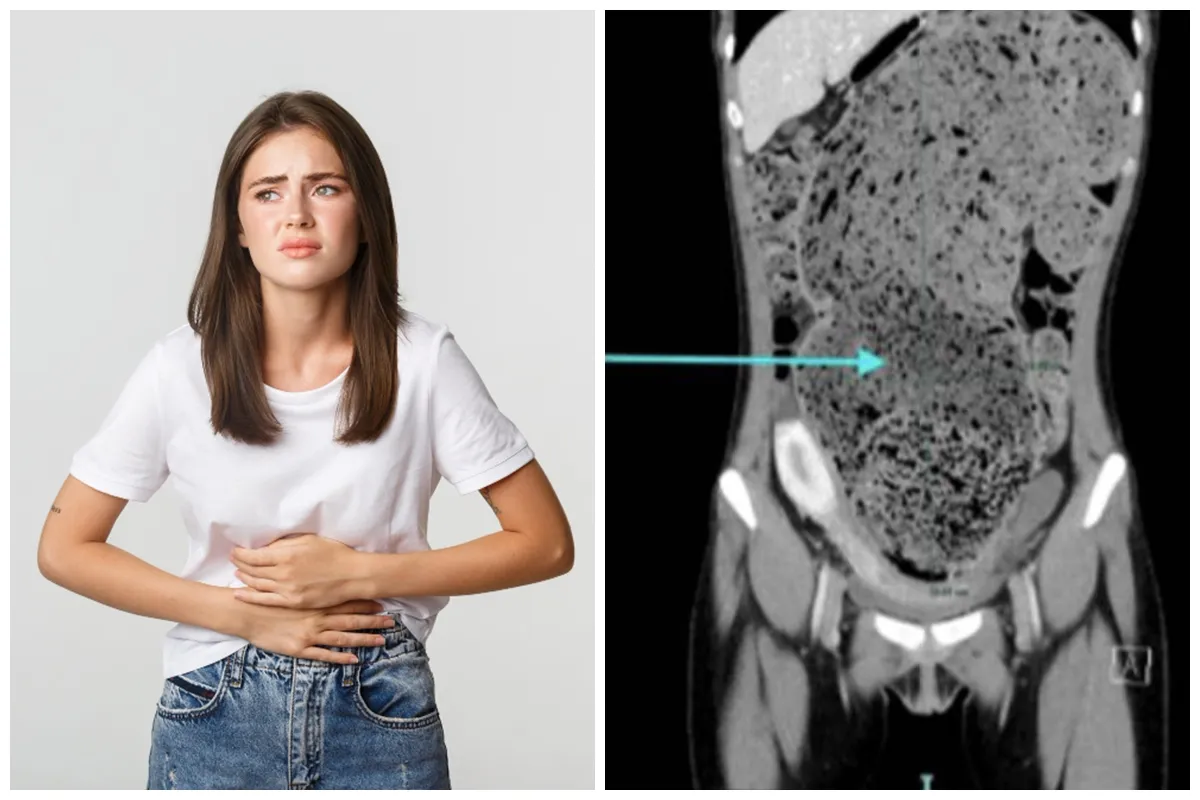

Kasus tersebut kemudian ditangani tim medis yang menemukan usus besar pasien memiliki ukuran abnormal. Ususnya melebar hingga 15 sentimeter dan penuh dengan tinja yang sudah lama mengeras.

Temuan medis itu dicatat dalam laporan yang dipublikasikan di jurnal Cureus. Dokter menggambarkan betapa sulitnya melakukan tindakan pemeriksaan karena tinja pasien terlalu padat dan keras.

Kondisi pasien membuat ususnya terlihat membesar secara signifikan. Dokter menggambarkan tekstur tinja yang dikeluarkan menyerupai tanah liat basah dan padat.

"Dokter mencatat usus besarnya mengalami pelebaran yang signifikan dan tinjanya menyerupai tanah liat yang padat/basah," imbuhnya.

foto: www.thesun.co.uk